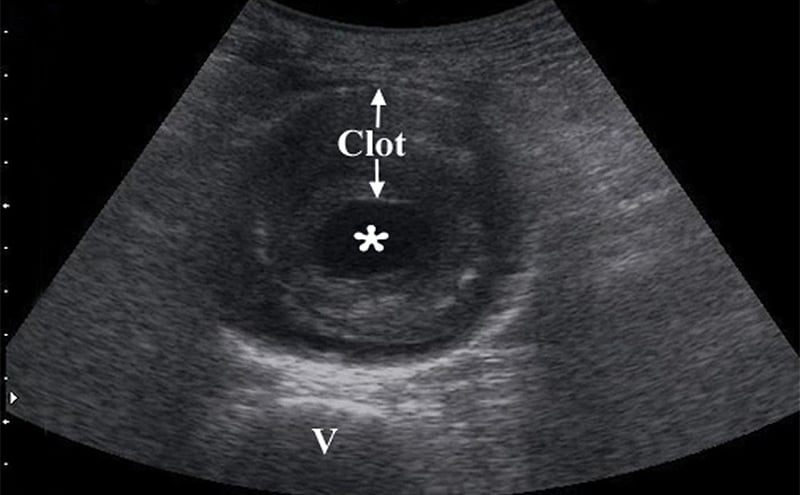

- Obtain measurements of aorta from outer wall to outer wall. Since aneurysms will often contain a thrombus, and with time this becomes calcified and hyperechoic, one may accidentally mistake the inner rim of the thrombus for the aortic wall. Doing this will lead a falsely decreased measurement of the true aortic diameter, possible causing the aneurysm to be missed completely.

- Figure 9. Transverse view of a 7 cm AAA with intraluminal clot (* on the lumen, “v” denotes vertebral body)